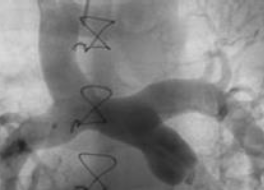

No plantão da UTI, encontra-se uma criança em pós-operatório imediato de cirurgia cardíaca. O procedimento realizado está ilustrado na figura a seguir.

São cuidados a serem tomados, EXCETO

Provas